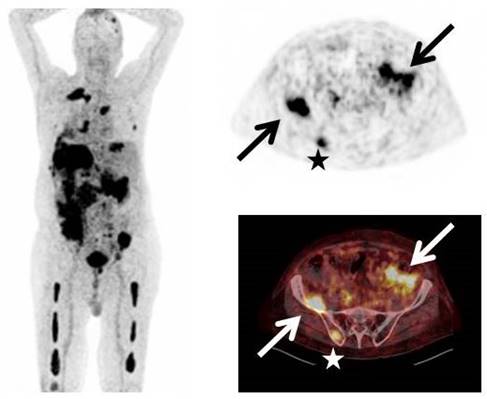

[68Ga]Pentixafor-PET was visually positive in 23/35 patients (65.7%, example given in Figure 1). In the remaining 12 subjects with serologically active disease, no relevant expression of CXCR4 could be recorded.

Figure 1

Display of a patient (patient #33) with MM Ig A λ and rising free serum light chains. [68Ga]Pentixafor-PET depicts intense tracer uptake in multiple intramedullary (stars) as well as extramedullary (arrows) lesions.